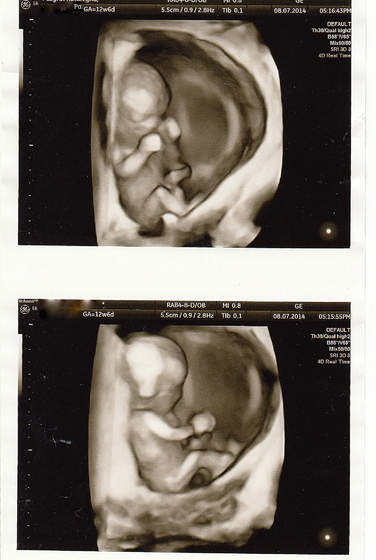

Hej ja po wizycie, bąbel młodszy o 2 dni niz z OM wiec mam sie za tydz pokazac na przeziernosc. Reszta ok, raczki, nozki, zoladek itd itd. Maluch ma 4,84 cm. Ja w pt ide na dokladne usg to moze cosik sie uda podgladnac a na razie taka tylko fotka na szybko. Tak sie wiercil maluch ze nie mozna bylo zrobic ladnego zdjecia